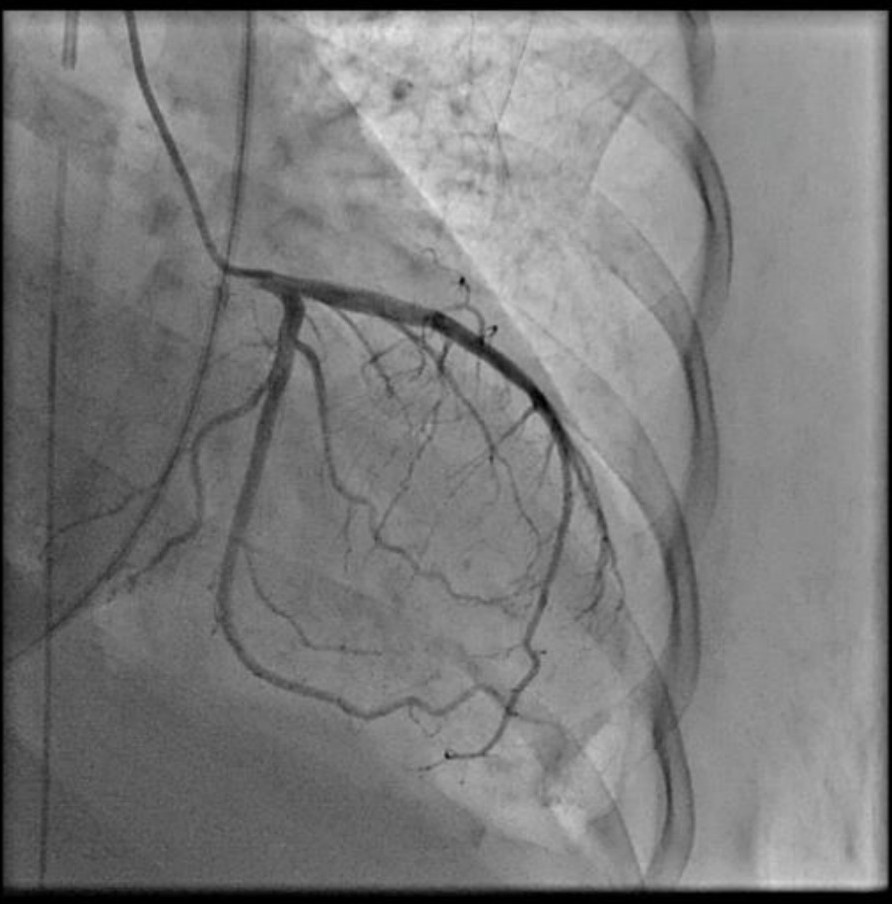

As STEMI could not be ruled out, immediate coronary angiography (CAG) was performed, revealing no significant coronary arteries stenosis. Despite optimal inotropes, cardiogenic shock persisted, prompting intra-aortic balloon pump (IABP) insertion during CAG

Based on the clinical presentation, ECG, and laboratory results, the initial working diagnosis was Anterior STEMI with KILLIP Class IV. CAG was then performed via radial artery using a 6-French introducer sheath, revealing no significant stenosis in the coronary arteries. As the cardiogenic shock still persisted despite optimal inotrope and vasopressor, an IABP was then inserted via femoral artery with the initial setting of 1:2 assist ratio. She was then transferred to the intensive care unit (ICU) where bedside echocardiography revealed a left ventricular ejection fraction (LVEF) of 48% without regional wall motion abnormalities, supporting a non-ischemic etiology. During hospitalization the patient developed acute kidney injury (AKI) with anuria. Further workup for myocarditis showed elevated C-reactive protein (CRP), high procalcitonin levels, and metabolic acidosis. Blood culture was sterile as she had been given antibiotic before. Given rapid clinical deterioration, broad-spectrum antibiotics (meropenem and cefoperazone) were initiated, and hemodialysis was performed. Her condition steadily improved throughout treatment. The IABP was successfully weaned off after four days, and inotropes were gradually tapered off. Serial ECGs also showed gradual resolution of the ST segment elevation and LBBB. After ten days of optimal antibiotics treatment, she continued to improve and was safely discharged from the hospital.